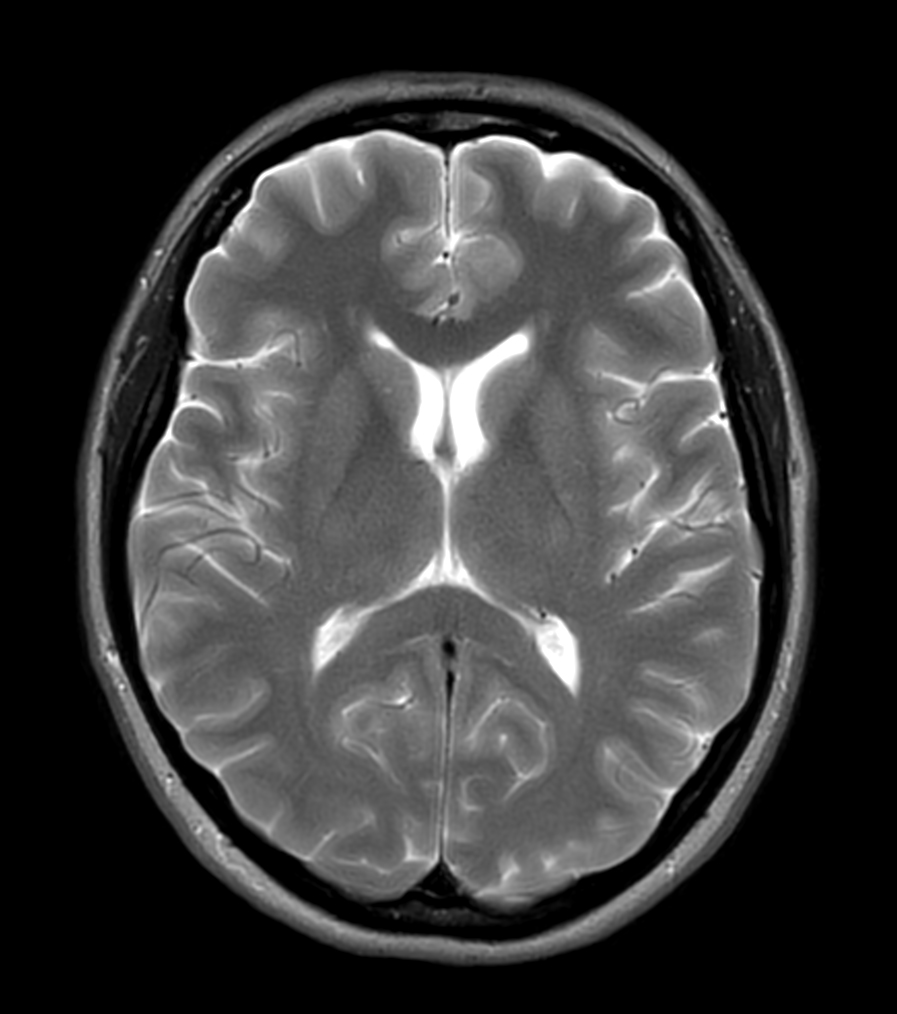

Axial T2w TSE MultiVane XD